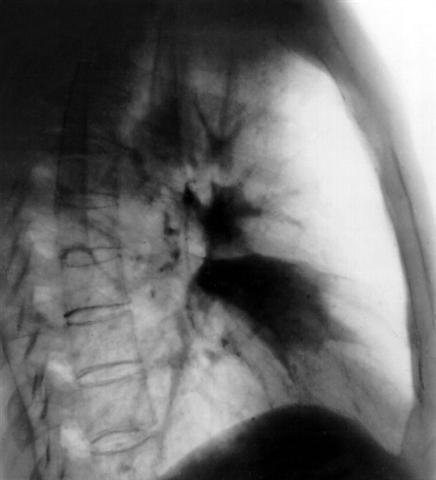

Рис. 3. Рентгенограмма грудной клетки (правая боковая прекция) при ателектазе IV сегмента правого легкого: интенсивное затенение в форме треугольника, обращенного вершиной к корню легкого.